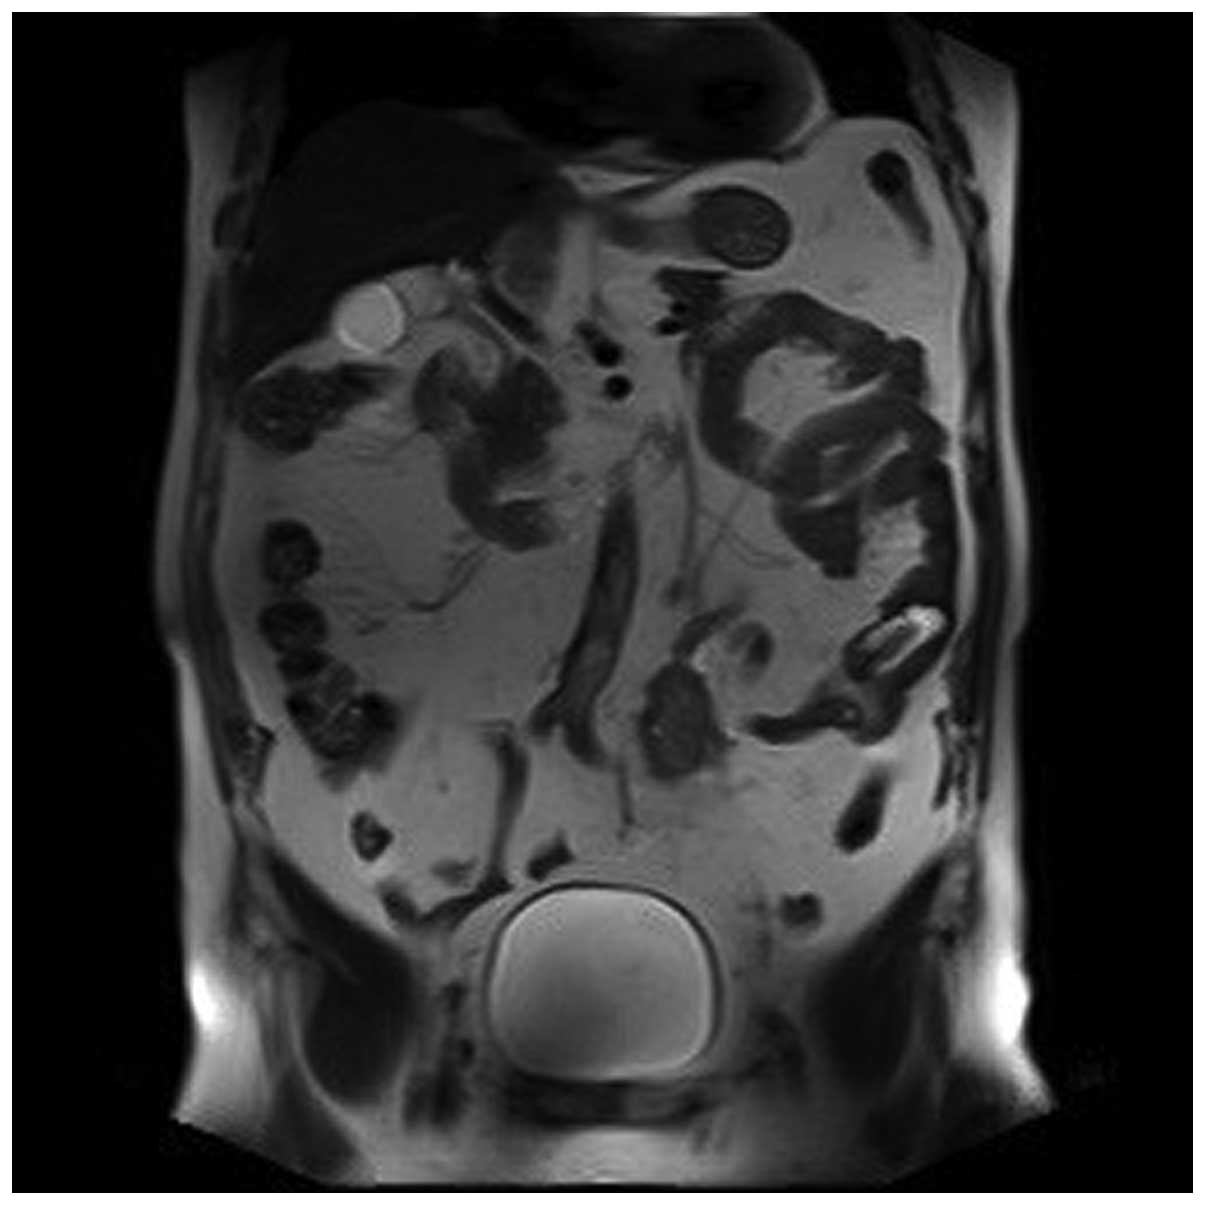

A 69-year-old Chinese Han male patient was admitted to the Department of Urology of Tianjin First Central Hospital (Tianjin, China) with a 10-month history of gross hematuria and 1-month history of left flank pain. The medical history of the patient included 17 years of hypertension, 20 years of coronary heart disease and an allergy to iodine. The findings of the physical examination were normal. The findings of the routine laboratory examinations were unremarkable. However, on urinalysis, there was macroscopic hematuria and 40–50 white blood cells per high-power field. On magnetic resonance imaging of the urinary tract, the iliac wing level around the left ureter exhibited an iso-intense T2 signal, an irregular mass with a rough outline and unclear boundaries of the corresponding level of the left iliac vessels. There was occlusion of the left ureter at the corresponding level, with hydronephroureterosis above the mass and undevelopment of the segment of the left ureter below the mass (Figs. 1, 2 and 3). The right kidney was normal. Chest radiographs were performed and revealed no primary or metastatic lung lesions. Left nephroureterectomy was performed and the clinical diagnosis was primary ureteral tumor. The gross examination revealed an ovoid, solid, white mass, sized 3.5×3.0×1.6 cm, originating from the ureteral mucosa and protruding into the ureteral lumen, with invasion of the periureteral adipose tissue. Examination under a light microscope revealed that the tumor was composed of atypical carcinoid cells with diverse shapes, with common mitotic figures, and small cells with a round to fusiform shape, scant cytoplasm, fine granular nuclear chromatin, and absent or inconspicuous nucleoli (Fig. 4). The tumor cells exhibited cytoplasmic positivity for cytokeratin (CK)7, epithelial membrane antigen (EMA), CD56 and synaptophysin, and negativity for neuron-specific enolase (NSE), chromogranin A (CgA) and CK20. The Ki-67/MIB1 index was 20%. The patient was diagnosed with NEC of the ureter with atypical carcinoid and small-cell carcinoma components. The postoperative recovery of the patient was uncomplicated; however the patient refused chemotherapy or radiotherapy. During the regular follow-up examinations, there was no evidence of tumor recurrence at 5 months postoperatively; however, he succumbed to extensive metastases after 12 months of follow-up.

Figure 2.

The iliac wing level around the left ureter exhibiting an iso-intense T2 signal and an irregular mass with a rough outline.